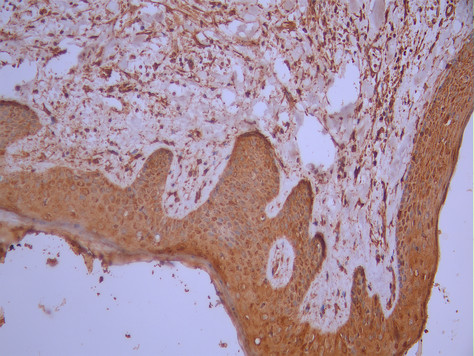

• IHC image of CSB-RA699080A0HU diluted at 1:100 and staining in paraffin-embedded human skin tissue performed on a Leica BondTM system. After dewaxing and hydration, antigen retrieval was mediated by high pressure in a citrate buffer (pH 6.0). Section was blocked with 10% normal goat serum 30min at RT. Then primary antibody (1% BSA) was incubated at 4°C overnight. The primary is detected by a Goat anti-rabbit polymer IgG labeled by HRP and visualized using 0.05% DAB.